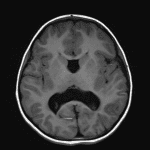

Middle Interhemispheric Variant (MIHV) of Holoprosencephaly

Findings

- Absent septum pellucidum and dysplastic corpus callosum with maintained fibers in the genu and splenium but thinned and dysmorphic appearance of the body and isthmus

- Fusion of the thalami at midline and cross-hemispheric fusion of supracallosal gyri with abnormal cortical thickening

- Colpocephalic ventricular morphology without evidence of hydrocephalus

- Nonspecific mild patchy T2/FLAIR signal hyperintensity in the periventricular white matter

- Abnormal cortical thickening along the posterior aspects of the right greater than left sylvian fissures with polymicrogyria

- Azygos anterior cerebral artery

Diagnosis

- Middle interhemispheric variant (MIHV) of holoprosencephaly

Constellation of findings most consistent with middle interhemispheric variant (MIHV) of holoprosencephaly including: absent septum pellucidum, thinned and dysmorphic appearance of the body and isthmus of the corpus callosum, fusion of the thalami at midline, and cross-hemispheric fusion of supracallosal gyri.

Abnormal cortical thickening and polymicrogyria along the posterior aspects of the right greater than left sylvian fissures as well as abnormal cortical thickening of the bridging supracallosal gyri, all potentially representing possible epileptogenic foci.

Colpocephalic ventricular morphology without evidence of hydrocephalus.

- Deficient interhemispheric fissure with failure of separation of the posterior frontal and parietal lobes

- Fusion of the thalami

- Sylvian fissures oriented vertically connecting across the midline over the vertex

- Body of the corpus callosum is usually deficient/dysplastic in the region of interhemispheric nonseparation, whereas the genu and splenium are more normally formed

- Septum pellucidum is usually absent, and the ventricles may show hypoplastic frontal horns

- Cortical dysplasias, heterotopias

- Azygos anterior cerebral artery